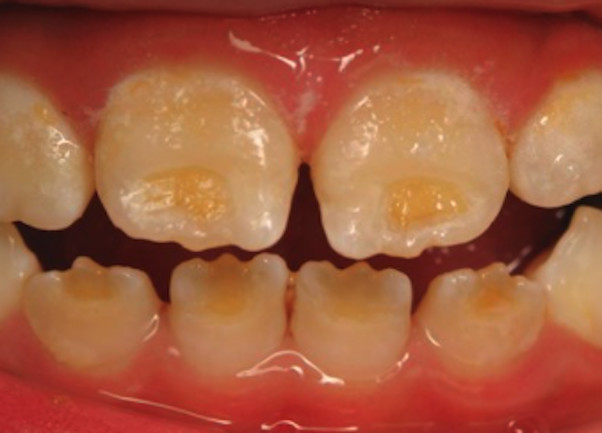

Enamel is the hard, protective outer layer of your teeth. Enamel hypoplasia is a defect of the enamel that only occurs while teeth are still developing. Still, it can affect both baby teeth and permanent teeth. The condition results in thin enamel, which makes your teeth vulnerable to dental decay.

The visual signs of enamel hypoplasia include white spots, pits, and grooves on the outer surface of the teeth.

Some of the signs of enamel hypoplasia are obvious, but others are more difficult to detect and may not be noticeable until they cause major dental problems. Having thin tooth enamel can lead to:

pits, tiny groves, depressions, and fissures

white spots

yellowish-brown stains (where the underlying layer of dentin is exposed)